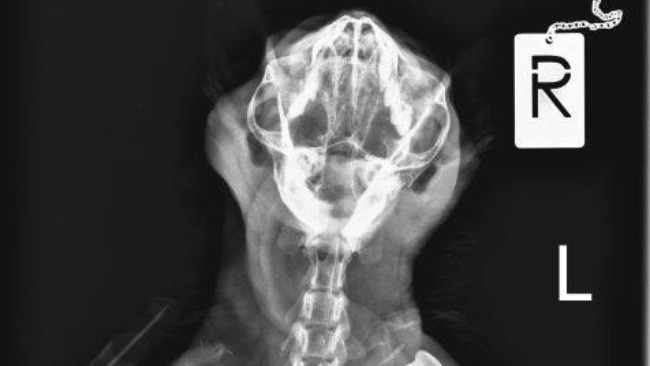

Po wielu telefonach znalazłam lekarza weterynarii - chirurga - który podjął się wykonania skomplikowanego zabiegu "naprawy" żuchwy. Koszt samej operacji to ok.2,5tys zł, pooperacyjny pobyt w szpitaliku, leki, potem usunięcie drutów - pewnie drugie tyle....

Kot dziś rano odebrany, późnym wieczorem dzwonił Pan Dr Oganiaczyk z informacją o przebiegi operacji.

Kot ma już dziób symetryczny, właściwie zamknięty - zdjęcia później.